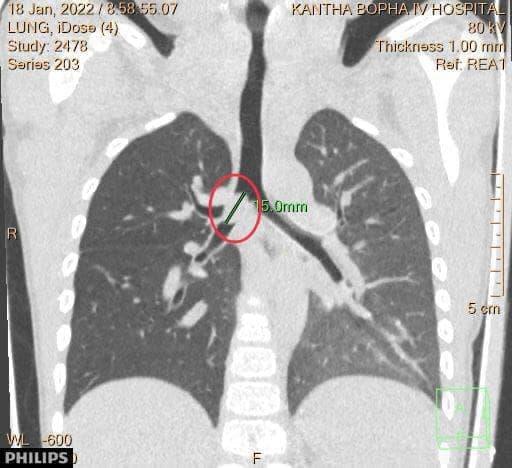

ភ្នំពេញ៖ នៅថ្ងៃទី១៨ មករា ២០២២ មន្ទីរពេទ្យគន្ធបុប្ជាបានឱ្យដឹងថា ក្មេងប្រុសតូច អាយុ៤ឆ្នាំ មកពីខេត្តស្វាយរៀង ចូលមកដល់មន្ទីរពេទ្យគន្ធបុប្ផាភ្នំពេញ ដោយដង្ហក់ស្ទះខ្យល់ដង្ហើមយ៉ាងធ្ងរបំផុត បណ្តាលមកពីឈ្លក់គ្រាប់ទៀប ចូលក្នុងទងសួតស្តាំ។

ក្រុមគ្រូពេទ្យឯកទេសសង្រ្គោះបន្ទាន់ និងក្រុមវះកាត់ បានជួយសង្គ្រោះជីវិតកុមារបានជោគជ័យ ។